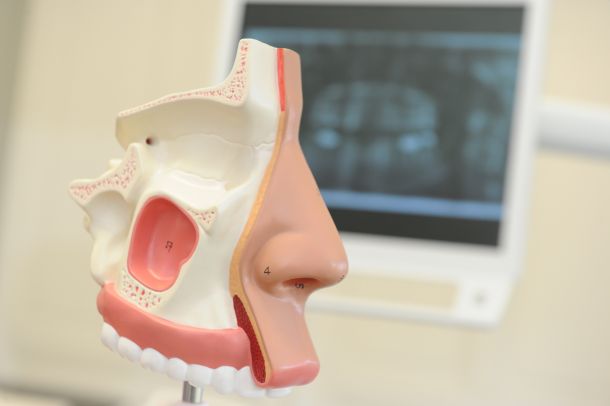

Unsere Behandlungen umfassen das komplette Spektrum von Erkrankungen, Verletzungen und Fehlbildungen. Angefangen bei kleinen chirurgischen Eingriffen bis hin zu aufwendigeren Operationen. Wir besitzen umfangreiche Erfahrung in der dentalen Implantologie und arbeiten, falls nötig, in Zusammenarbeit mit Ihrem Zahnarzt um für Sie das bestmöglichste Behandlungsergebnis zu erzielen.

Als Ihr engagierter Facharzt für Mund-Kiefer-Gesichtschirurgie bringe ich eine tiefe Kenntnis der komplexen Strukturen von Gesicht und Gebiss in jede Behandlung ein. Mein beruflicher Weg ist geprägt von der Leidenschaft, das Wohlbefinden meiner Patienten durch ein breites Spektrum chirurgischer Eingriffe – von kleineren Korrekturen bis zu umfangreichen Operationen – zu verbessern. Die dentalen Implantologie stellt dabei einen meiner Schwerpunkte dar, in dem ich durch langjährige Erfahrung und stetige Weiterbildung herausragende Ergebnisse erziele.

3D Röntgen/ DVT

DIE DIGITALE VOLUMENTOMOGRAPHIE DES OBER- UND UNTERKIEFERS IST DIE DERZEIT MODERNSTE UND SCHONENDSTE RÖNTGENTECHNIK IN DER ZAHNHEILKUNDE UND MUND-, KIEFER- UND GESICHTSCHIRURGIE.

Mit Hilfe dieser Technik können wertvolle diagnostische Informationen über die Lage von Nerven, die Knochenstruktur und die Erkrankungen von Zähnen im Kieferknochen gewonnen werden.